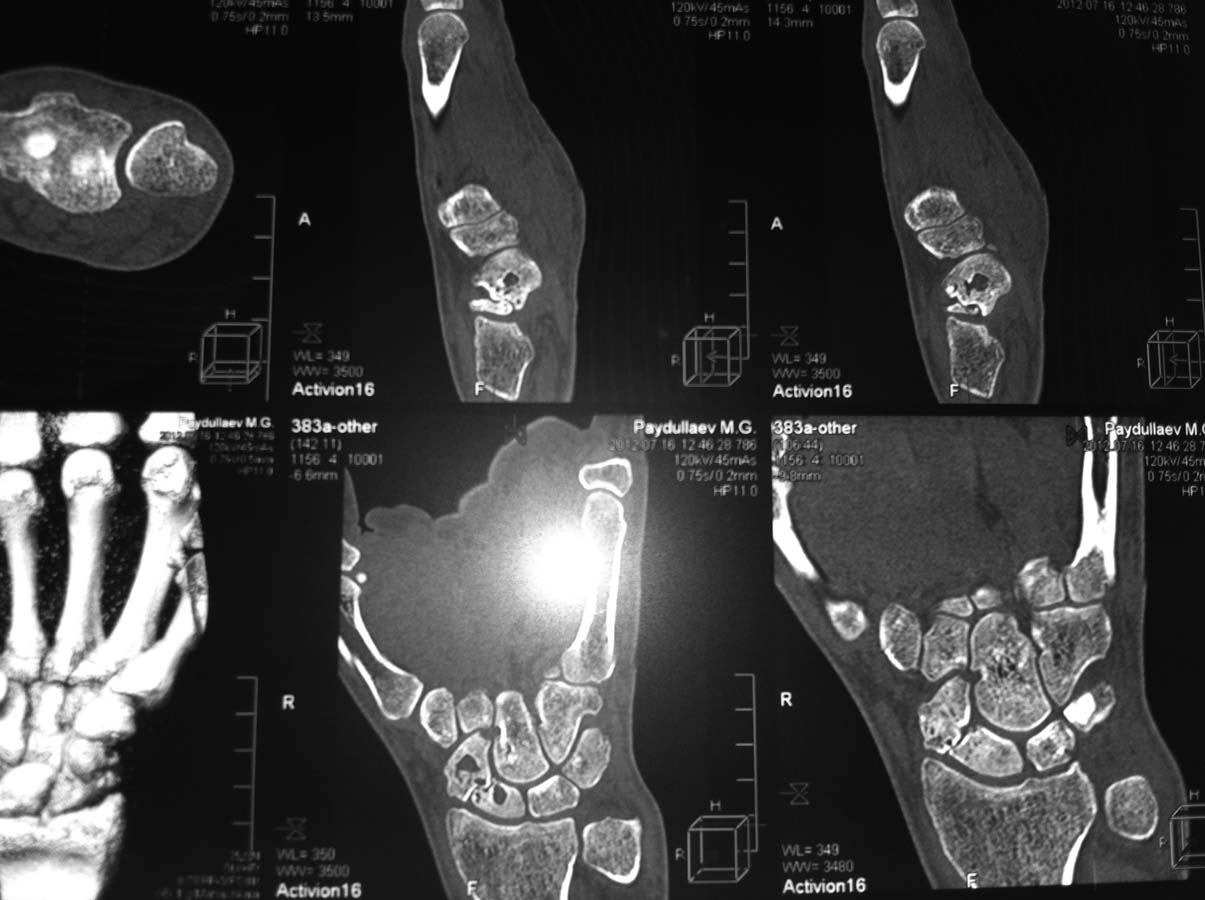

Здравствуйте. Обратился пациент, 28 л. , травма 7 мес. назад, получал лечение: 2 мес. гипс, курс физиотерапии, ЛФК. Жалуется на постоянные ноющие боли в кистевом суставе.

Локально: кожный покров в области лучезапястного сустава визуально не изменен, отмечается незначительный отек мягких тканей, болезненность при пальпации в проекции тыльной и наружной поверхности лучезапястного сустава, движения в суставе умеренно ограничены, болезненны. Рентгенограммы малоинформативны. Больному выполнена СКТ. Готовим на операцию: наложение дистракционного спицевого АВФ на 2мес. Хотелось бы узнать мнения коллег. Спасибо.

1. "Стыдно признаться, но асептического некроза не заметил." - на снимках видны кисты в отломках ладьевидной кости, что является признаком асептического некроза кости.

Однако доступных данных, касающихся данного случая недостаточно, чтобы это утверждать". - Ну, если мы у каждого больного с ложным суставом ладьевидной кости будем подозревать болезнь Прайзера, то мы далеко пойдем. Поэтому полностью согласен с Вами, что если нет убедительных и доступных данных на данный момент, то выдумывать и утверждать ничего не надо. На приведенной СТ есть характерные признаки аваскулярного асептического некроза хотя бы в одном из отломков? Нет таких признаков. Вот и вся логика. Есть картинка ложного сустава с выраженной кистовидной перестройкой и небольшим смещением отломков.

В классификации иностранных авторов (имею ввиду Herbert) видимо под термином  "fragmentation" скрываются наши кисты и псевдокисты. Хотя может я и ошибаюсь".- Давайте, опять же, ничего не додумывать за кого-то. Под термином "фрагметация" понимается одна картинка, под термином "киста/псевдокиста/кистовидная перестройка", "резорбция" и т.д понимаются абсолютно другие состояния. Так вот состояние под названием асептический-"аваскулярный некроз" именно ладьевидной кости и именно при ложном суставе, а не болезни Прайзера или Кинбека, подразумевается следующая СТ-картинка:"The 2 signs that significantly correlated with AVN were increased radiodensity of the proximal pole (often termed sclerosis) and the absence of converging trabeculae between the fragments".-G.A. Buijze, L.Ochtman, D.Ring. Management of Scaphoid Nonunion.CURRENT CONCEPTS.//J Hand Surg 2012;37A:1095–1100.

Или то же самое в другой работе:"Smith et al. also evaluated scaphoid non-unions utilizing

computed tomography [10]. This study revealed increased radiodensity of the proximal pole and absence of any converging trabeculae between the fracture fragments as the most significant determinants of avascular necrosis".- Min Jung Park, A.T.Lee, J.Yao. An unusual case of spontaneous healing of a proximal pole

scaphoid non-union. // HAND (2011) 6:313–316. Все четко и ясно - речь идет не в общем об AVN, а именно об AVN при ложном суставе и СТ-диагностике этого состояния, то есть все, как в данной теме и на компьютерной томограмме. Поэтому ничего додумывать не надо. Всех перечисленных признаков асептического аваскулярного некроза на представленных СТ-картинках нет, поэтому и AVN нет.